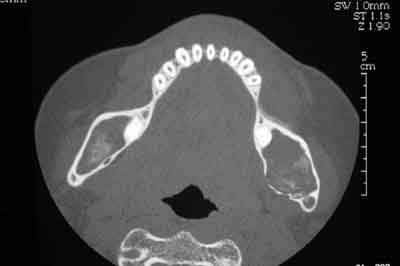

Femme de 40 ans. Aucun antécédent (notamment chirurgical) en dehors d'un DNID, d'un tabagisme modéré (5 paquets-année) et d'une surcharge pondérale. Consulte pour apparition progressive d'une volumineuse voussure dans les 2 vestibles inférieurs et d'une modification consécutive de la forme de la partie inférieure de son visage. A l'examen clinique : tuméfaction dure et fixée dans les 2 vestibules. Sensibilité (V3) normale. Gencive normale. Dents restantes non mobiles, vitales. Pas d'adénopathies palpables. Biologie non faite pour l'instant. Je vous joinds l'OTP et le scan. Diagnostic et options de traitement?

Bref, en ce qui concerne ce cas (assez récent), je vous livre le raisonnement qui a été le notre : probables kystes péricoronnaires sur les dents incluses (il n'y a pas de dents "surnuméraires"...). Décision d'abord chirurgical pour énucléation des 3 kystes (les ponctions ne "marchent" pas dans ces lésions) et examens anatomopathologiques extemporanés pour décider, en per-opératoire, de la conduite à tenir (photo 1).

Diagnotic extemporané : kératokystes (!). Les dents incluses se sont donc avérées être un piège diagnostic! Le traitement s'est de ce fait contenté d'un curetage appuyé des paroies osseuses, conservation des 2 nerfs dentaires et, en raison de la taille des kystes mandibulaires et du risque de fracture post-opératoire, nous avons y avons associé une greffe (hydroxyapatite + os autologue (crête illiaque) + PRP) au niveau mandibulaire uniquement (photos 2 et 3)et blocage intremaxillaire pendant 15 jours.